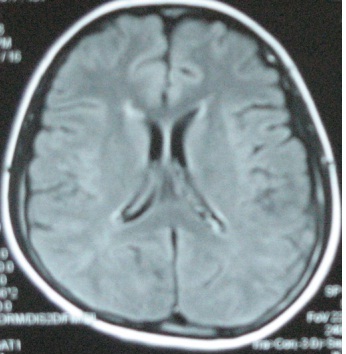

Hình ảnh chụp MRI sọ não trước và sau điều trị

Bệnh nhân được tiến hành điều trị hoá chất phác đồ CHOP  8 đợt và tiêm Methotrexat nội tuỷ, kết quả u sọ não tan hoàn toàn. Đến nay, bệnh nhân đã được ra viện 10 tháng. Hiện tại vẫn khoẻ mạnh, chụp MRI sọ não không phát hiện ra khối u.